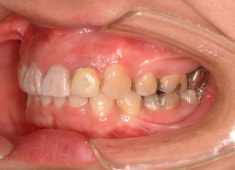

治療開始から1年8ヶ月後